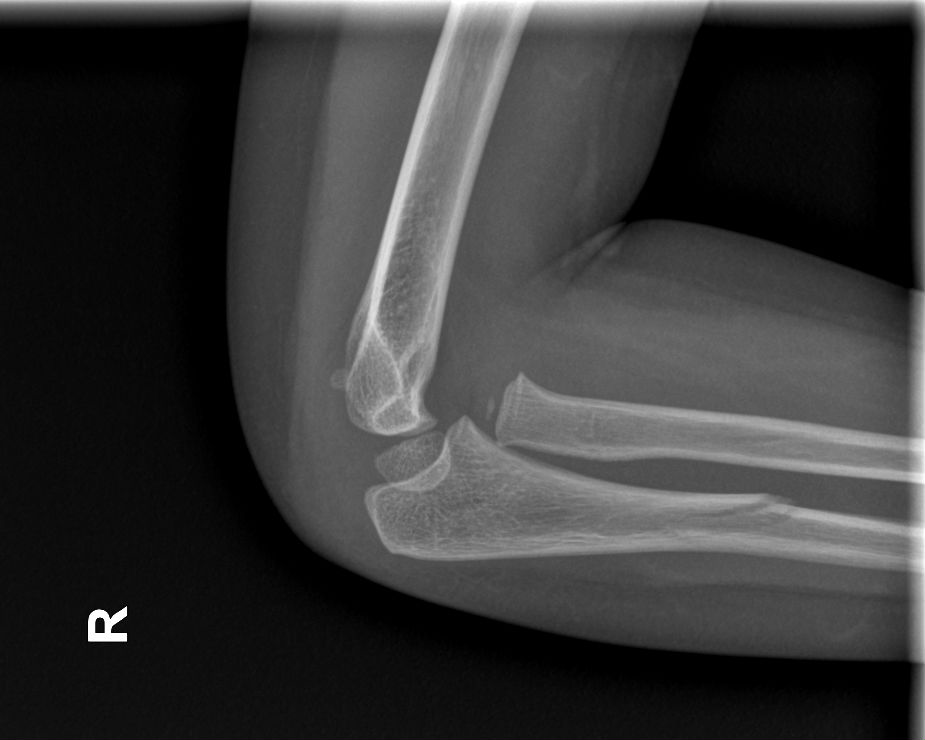

¿Qué le pasa a este codo?

Niña de 3 años que acude al Servicio de Urgencias Pediátricas por dolor en el antebrazo derecho tras una caída. La madre refiere que no ha habido mecanismo de tracción. Tras la administración de analgesia, la paciente continúa con impotencia funcional y supinación mantenida.